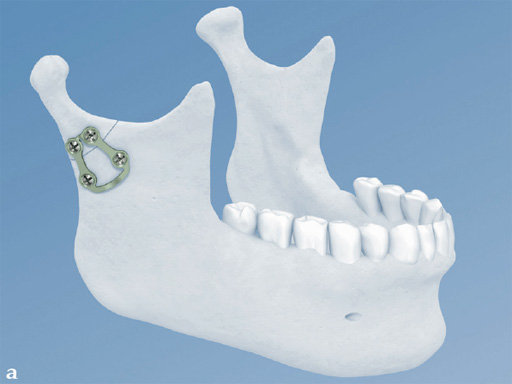

Lambda Plate

The lambda plate comes in a left and right version. It emulates a two-plate technique as its specific shape and 7-hole design with the width of a single plate at the top segment allows the surgeon to advance the lambda plate high up into the very narrow zone of the condylar neck just below the head. The fixation arms straddle the mandibular canal to avoid injury risk of the inferior alveolar nerve.

The lambda plate can be placed using retromandibular or submandibular surgical approaches. For positioning, the straight 5-hole segment is placed parallel to the posterior ramus border aligned with the condylar head. If required the anterior arm may be bent to fit the bony surface below the sigmoid notch.

Both plates are based on the matrix mandible system platform. Therefore, they are compatible with the existing matrix instrumentation and use the established color-coding for easy identification in the operating room. Both are 1.0 mm thick and malleable (green-grey color coding) and manufactured from commercially pure titanium.